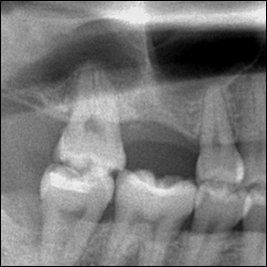

術前レントゲン写真

歯の根っこが割れているのが分かります。